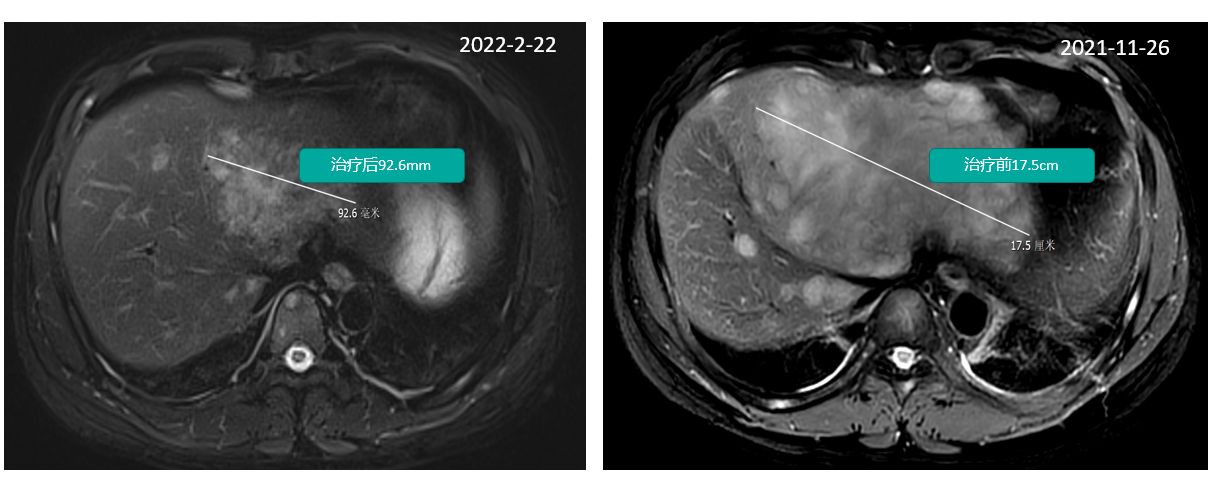

1. 治疗2月后CT评估显示肝转移病灶从18cm缩小至7cm

CT评估显示肝转移病灶从18cm缩小至7cm